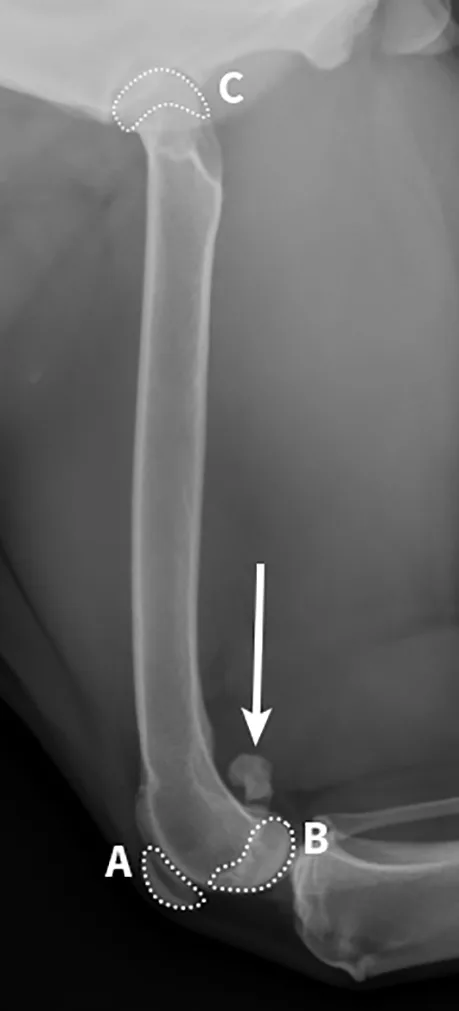

On the radiograph, the medial and lateral condyles should be almost perfectly superimposed (B). The patella (A) should be cranial, and the medial and lateral fabellae should have near superimposition to each other (arrow). In a straight lateral femoral view, the femoral head (C) should be slightly cranial and dorsal to the femoral diaphysis due to the femoral neck anteversion.